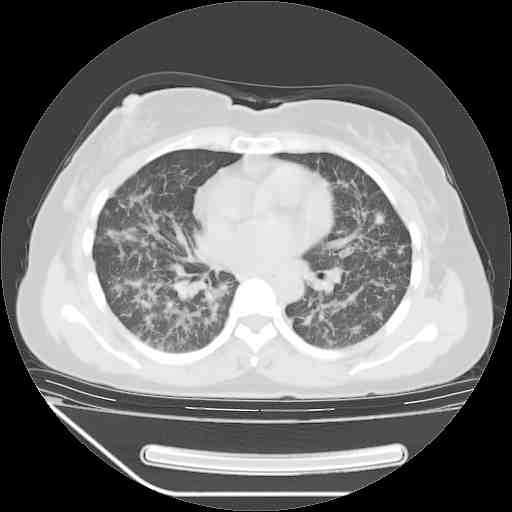

下面是今天刚刚做的,在上海治疗,吃了家属也说不清的一种药,一个月1万左右,

考虑  腺癌肺内转移,治疗较前病灶缩小、减少

支持肺癌并肺内淋巴管炎,  原发灶小了,但转移较前片明显了.

支持右肺下叶周围型肺癌并肺内淋巴管炎,  原发灶小了,但转移较前片明显了.。

标准的细支气管肺泡癌呀!治疗后病情有所控制,也没治愈的迹象!

支持右肺下叶周围型肺癌并肺内淋巴管炎;病灶有所控制。